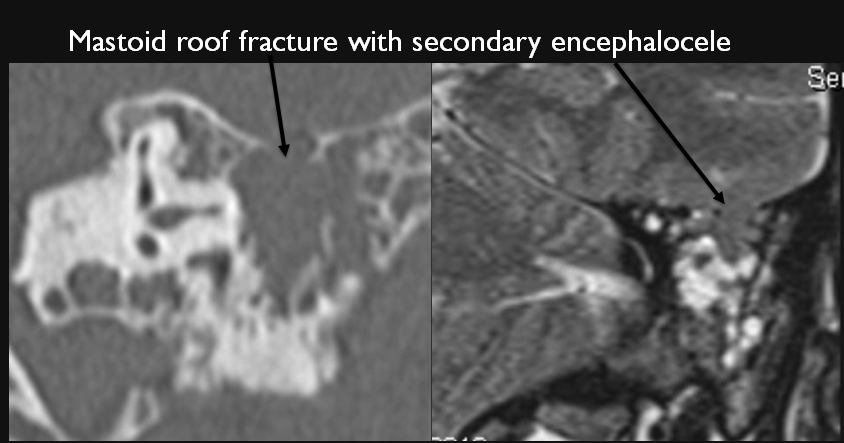

The roof of the mastoid and/or middle ear is fractured.

A possible meningocele and/or encephalocele or CSF leak is present.